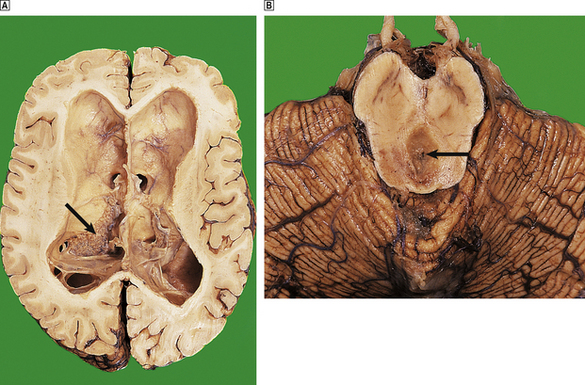

Herniations occur at several characteristic sites within the cranial cavity, depending on the site of the space-occupying lesion (Fig. 26.5). Transtentorial herniation is frequently fatal because of secondary haemorrhage into the brainstem (Fig. 26.6). This is a common mode of death in patients with large intrinsic neoplasms or intracranial haemorrhage.

image

Fig. 26.5 Sites of intracranial herniation. Space-occupying lesions in the cerebral hemispheres may cause herniation of the cingulate gyrus under the falx cerebri (1) or of the hippocampal uncus and parahippocampal gyrus over the tentorium cerebelli (2). Cerebellar tonsillar herniation through the foramen magnum (3) can occur with lesions in the cerebrum or cerebellum. A swollen brain will herniate through any defect in the dura and skull (4).

Fig. 26.6 Herniation effects in the brain. image A large haemorrhagic neoplasm (glioblastoma) is present in the right cerebral hemisphere, causing shift of the midline structures to the left and compression of the right lateral ventricle. image Transtentorial herniation at the base of the brain. A prominent groove surrounds the displaced parahippocampal gyrus (arrow). The adjacent 3rd nerve (N) is compressed and distorted and the ipsilateral cerebral peduncle (P) is distorted with small areas of haemorrhage.